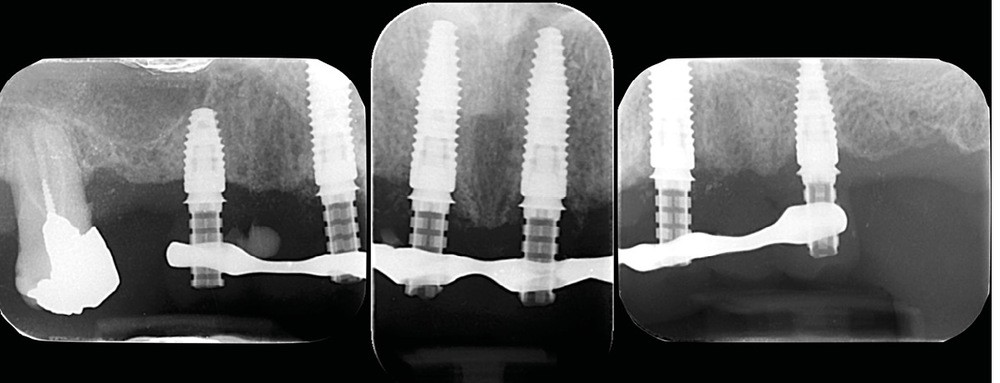

Après une étude prothétique [4, 5], il est décidé de procéder à l’extraction des dents maxillaires résiduelles (sauf une molaire qui servira pour enregistrer l’occlusion et qui sera avulsée dans un second temps), avec une implantation immédiate de 6 implants maxillaires et une mise en charge immédiate d’un bridge provisoire. Les implants se distribuent sur l’arcade ; des aménagements sous-sinusiens ne sont pas nécessaires (fig. 4 à 6).

Des implants mandibulaires postérieurs sont également programmés dans la même séance.